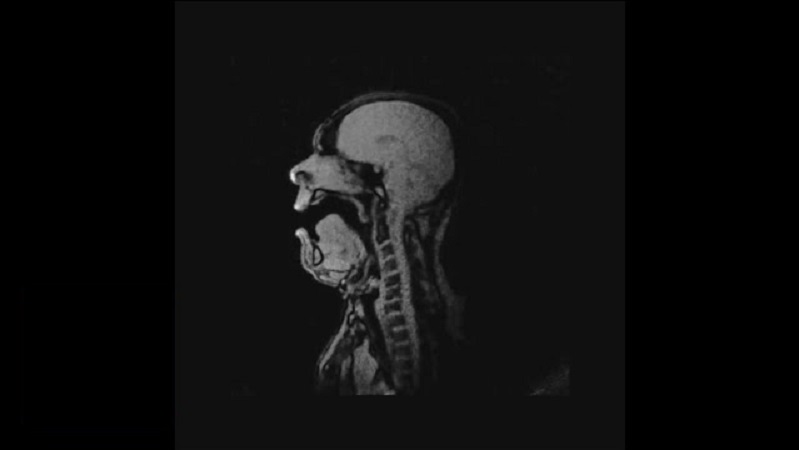

MRI에서가 수

독일 프라이 부르크 음악의 의학 연구소 5월 4일 (수요일)을 수행 MRI를, 실시간으로 독일 작곡가 탄호이저 오페라에서 노래를 수행 하는 오페라가 수 마이클 Volle 표시.

MRI는 wtorinolaryggologikoy 프로젝트의 일환으로 제작 되었습니다와 오페라가 수의 입 안으로 어떻게에 관한 연구, 노래를 할 때.